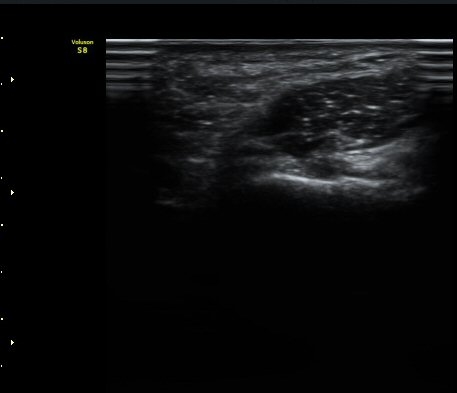

Guyon's canal ±ÙÀ§ºÎ ¿ÜÃø¿¡¼­ ô°ñ½Å°æ ½ÉºÎ°¡Áö(DUN)°¡ °üÂûµÇ°í ½ÉºÎ¿¡ °¥°í¸®»À(hamate)

°í¸®(hook)°¡ Èñ¹ÌÇÏ°Ô °üÂûµÈ´Ù(±×¸²1)